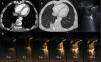

(A and B) Chest CT after intravenous administration of iodinated contrast medium, in the mediastinal window (A) and lung (B), showing a subpleural solid nodule (white arrow) with adjacent pleural thickening (black arrow) and bronchovascular incurvation (gray arrow). (C) Chest B-mode ultrasound: rounded consolidation (white arrow) associated with focal pleural thickening (black arrow). (D) Series of contrast-enhanced ultrasound images (time since administration of contrast appears in each image), demonstrating rapid uptake, earlier than 6seconds, that immediately becomes homogeneous and is not eliminated after more than a minute.

Although the radiological findings suggested rounded atelectasis, the suspicion of some lesion growth in the latest follow-up led us to rule out a malignant etiology. In this setting, we decided to perform ultrasonography with SonoVue® intravenous contrast (Bracco, Amsterdam, Netherlands) (Fig. 1C and D), with image-guided biopsy. Early (in the first 6seconds following administration), homogeneous uptake of the intravenous contrast medium by the tumor was observed on ultrasound. This uptake was maintained over time, and continued to be visible more than 1minute after the administration of contrast medium. These findings are highly suggestive of atelectasis. The biopsy results showed no atypia or other findings suggestive of a neoproliferative process.